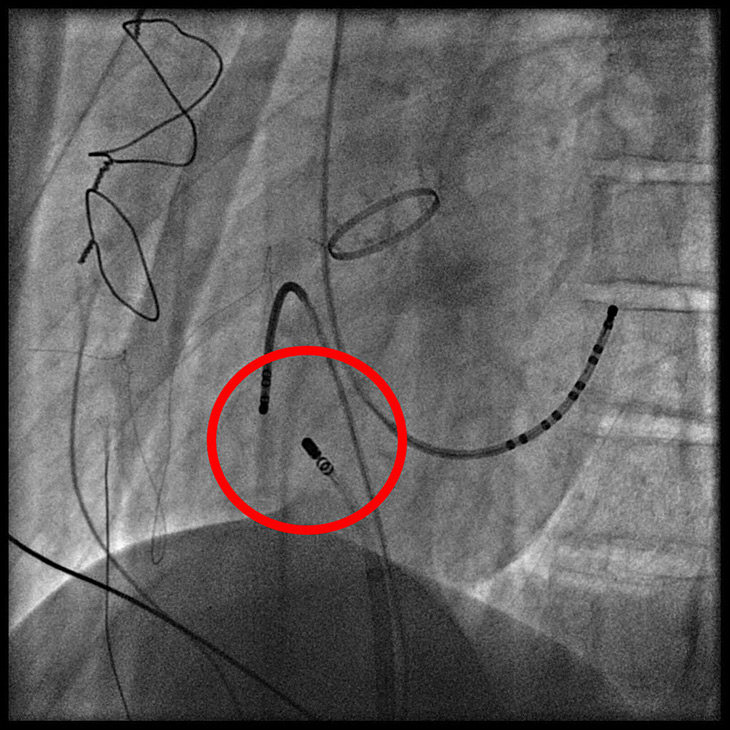

3D立體心臟圖,白色圈圈為心律不整最初始

電燒導管燒灼病灶。

蔡文欽醫師說,為了找出病人心律不整最初始的放電點,必須誘發心律不整發作,但鍾先生每次發作時血壓都很低,所以選擇全身麻醉的方式進行術式,由麻醉部團隊協助控制血壓,醫師就能專心進行術式,從鼠蹊部將高密度定位導管置入血管送往心臟,再以3D立體定位找出初始放電點後,使用電燒導管將病灶燒灼掉,整個手術過程約兩個小時能完成。